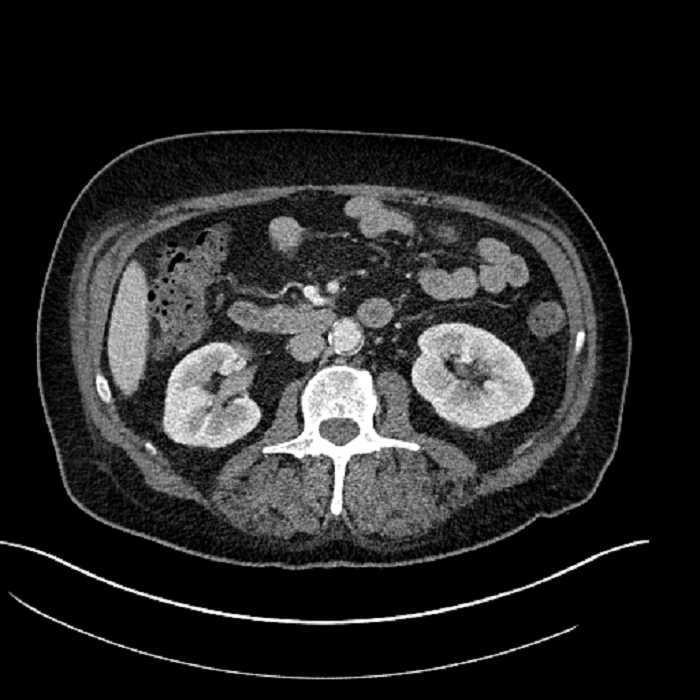

• Mild mural thickening of a segment of the sigmoid colon with adjacent fat stranding and a 1.5 cm fluid and gas collection along the tip of an inflamed diverticulum

• Loss of the normal fat plane between this collection and adjacent loops of small bowel, which demonstrate mural thickening

• No bowel obstruction

Acute sigmoid diverticulitis complicated by a small contained perforation and a large abscess in the right hepatic lobe. Additional small subcapsular abscesses along the anterior margin of the left hepatic lobe.

Additionally, loss of the normal fat plane between the peridiverticular collection and adjacent thickened loops of small bowel raises the potential for an enterocolonic fistula.

Hepatic abscess showing the double target sign with low density internally surrounded by a thin inner enhancing rim (red arrow) and ill-defined outer low density rim (yellow arrow). Blue arrow indicates an internal septation. Red arrows: additional smaller subcapsular abscesses. Red arrow: focal contained perforation associated with diverticulitis.